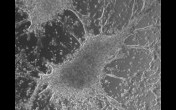

beating cardiomyocytes